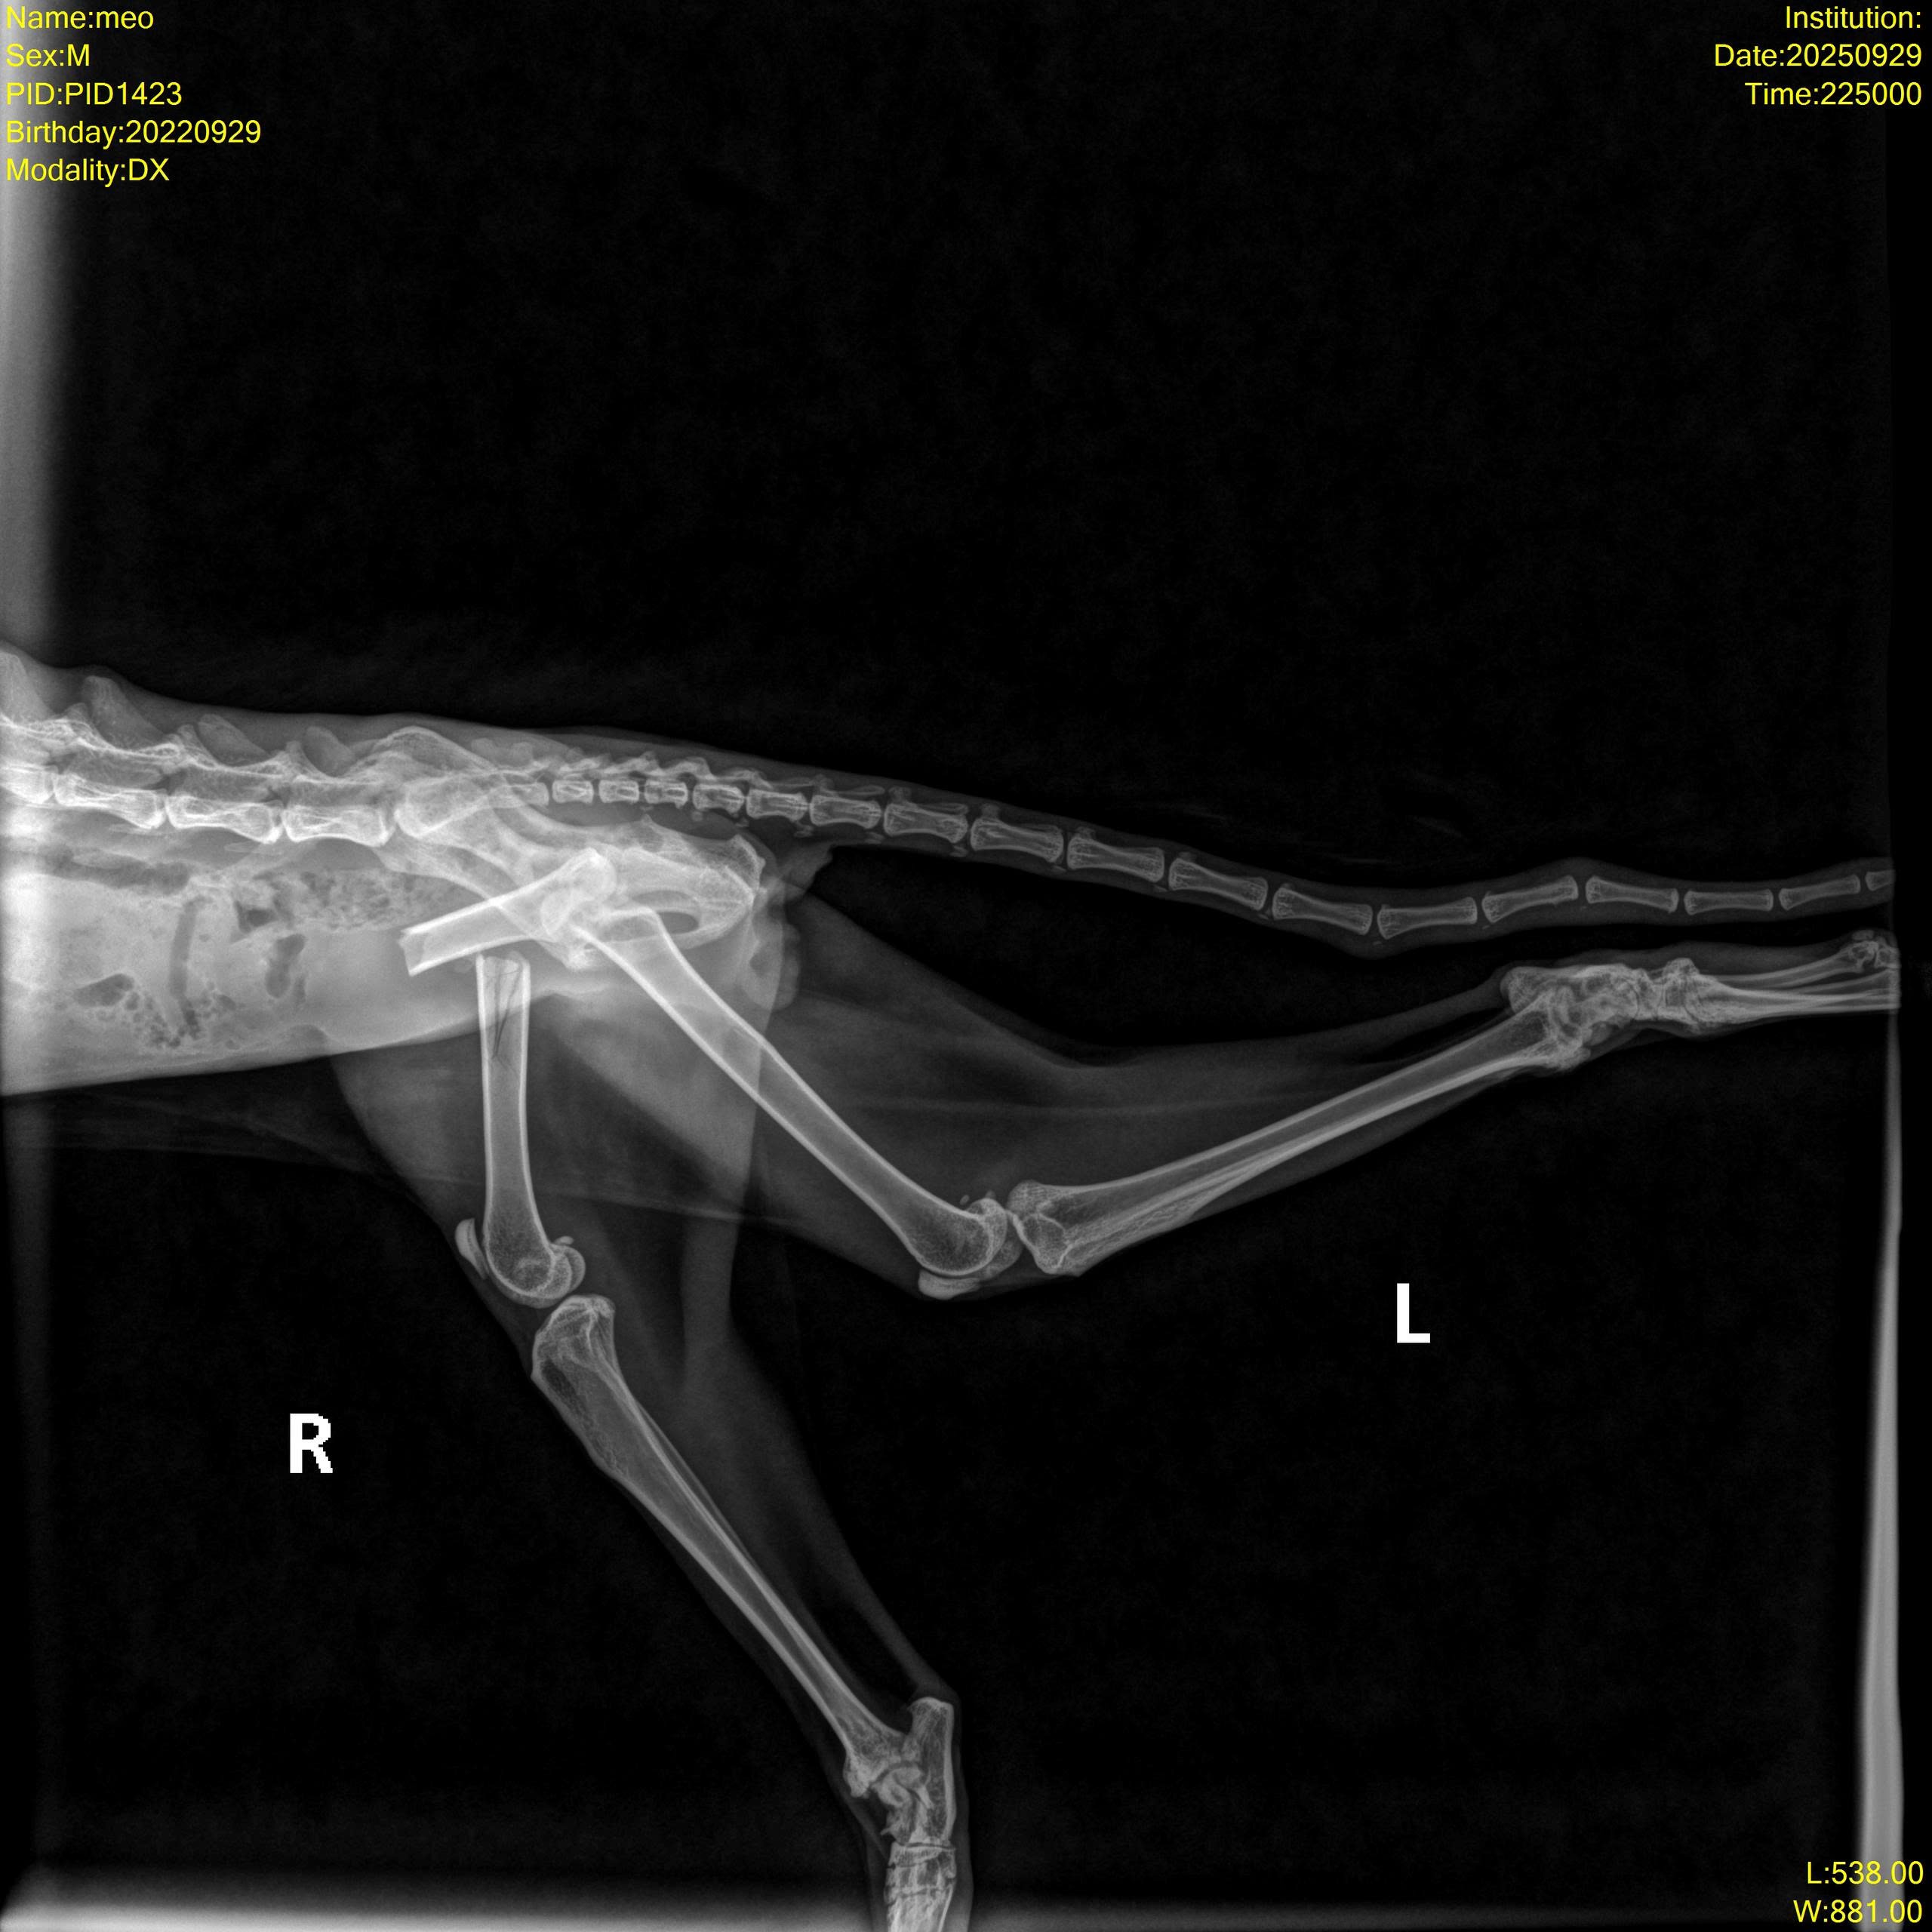

Một bạn nhặt được bé ngoài đường Mèo đực đã thiến, thể trạng gầy gò, mất nước. Niêm mạc nhợt nhạt, hai chân sau yếu, cham vào sẽ kêu đau. Trên người có vết cạo xước mất lông